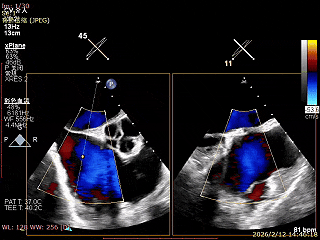

二尖瓣术前评估

复查TTE及TEE检查进一步评估二尖瓣情况。明确为AFMR,二尖瓣功能性反流,2区瓣叶运动,重度FMR(3+),肺静脉逆向血流;2区后叶长度13 mm,2区前叶长度20mm,AP径37mm,瓣口面积4.08cm²,房间隔高度4.5cm,瓣叶无钙化,二尖瓣瓣膜条件适合行TEER手术。

术前Bicom

二尖瓣2区功能性反流

二尖瓣三维视图

2区彩色血流